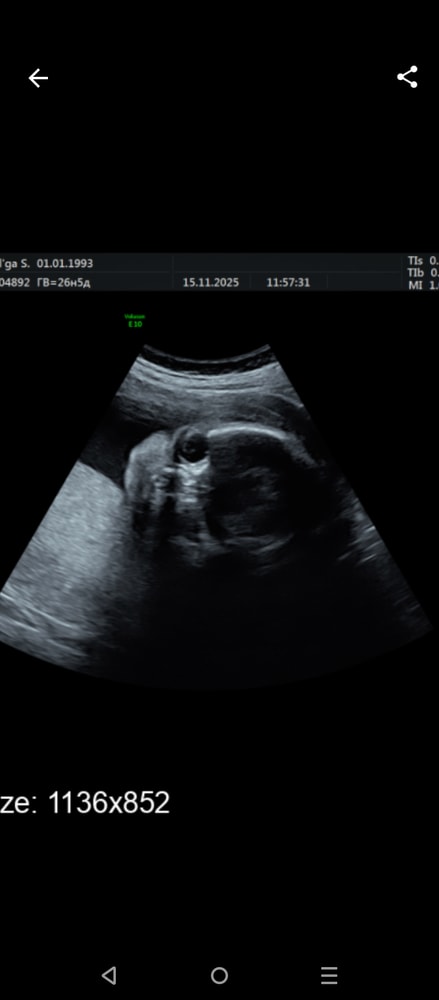

Сходила на УЗИ) 26,5

Шейка аж 62, узистка раза три перемеряла, говорит редкость, короче человек сам точно не вылезет 😁

Всё хорошо) а то я после антибиотиков переживала)